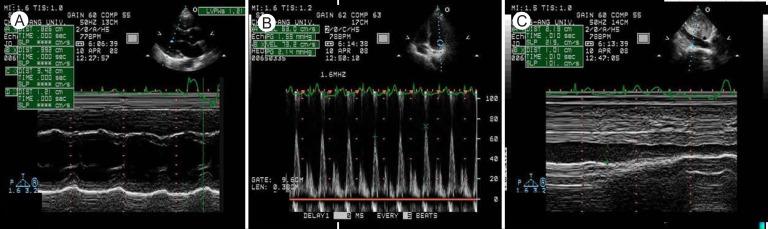

Acute myopericarditis is usually caused by viral infections, and the most common cause of viral myopericarditis is coxsackieviruses. Diagnosis of myopericarditis is made based on clinical manifestations of myocardial (such as myocardial dysfunction and elevated serum cardiac enzyme levels) and pericardial (such as inflammatory pericardial effusion) involvement. Although endomyocardial biopsy is the gold standard for the confirmation of viral infection, serologic tests can be helpful. Conservative management is the mainstay of treatment in acute myopericarditis. We report here a case of a 24-year-old man with acute myopericarditis who presented with transient effusive-constrictive pericarditis. Echocardiography showed transient pericardial effusion with constrictive physiology and global regional wall motion abnormalities of the left ventricle. The patient also had an elevated serum troponin I level. A computed tomogram of the chest showed pericardial and pleural effusion, which resolved after 2 weeks of supportive treatment. Serologic testing revealed coxsackievirus A4 and B3 coinfection. The patient received conservative medical treatment, including nonsteroidal anti-inflammatory drugs, and he recovered completely with no complications.